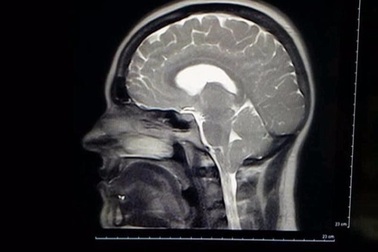

Không dám cười to vì sợ... thủng màng nãoMột người phụnữ đã phải tránh cười lớn một cách rất khổ sở do cô mắc một chứng bệnh kỳlạ: Cứ cười lớn là não bị rò rỉ dịch.